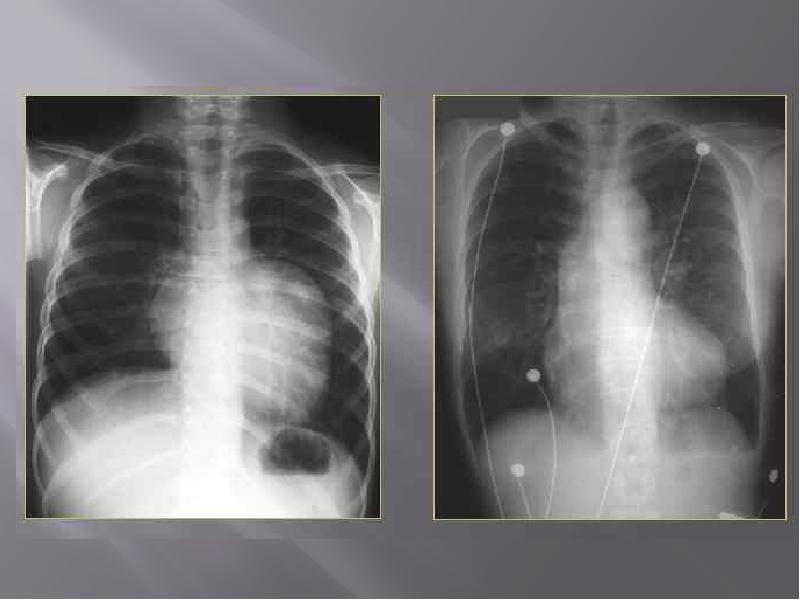

- 2. Синдром обширного просветления Синдром обширного просветления представляет собой повышение прозрачности

- 4. Тотальное двустороннее просветление наиболее часто дают эмфизема легких и гиповолемия малого

- 6. Тотальным односторонним просветлением чаще всего отображаются клапанное нарушение проходимости главного бронха,

- 9. Субтотальное одностороннее просветление наблюдается при клапанном нарушении проходимости долевого бронха в